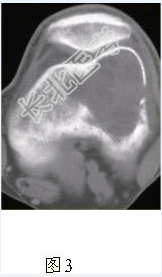

- [材料题] 患者女,35岁,左膝关节隐痛1年余,近1周加重,活动后明显疼痛。查体:左股骨下端外侧肿胀,压痛。行左膝关节正侧位CR,并行左膝关节CT扫描,见下图。

- 简答题1、根据膝关节CR和CT影像,你认为此病例的影像学表现有?

- 简答题2、对本病例,应首先考虑的诊断是?